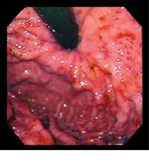

Васкуло- и гастропатия – это совокупность макроскопических проявлений, наблюдаемых в слизистой оболочке пищевода и желудка при портальной гипертензии, связанных с эктазией и дилятацией сосудов слизистого и подслизистого слоев без значительных воспалительных изменений (рис. 2).

• Легкая - небольшие участки розового цвета, окруженные белым контуром.

• Средняя - плоские красные пятна в центре розовой ареолы

• Тяжелая - сочетание с точечными кровоизлияниями

Рис. 2. Степени гастропатии: I – легкая, II – средняя, III – тяжелая.